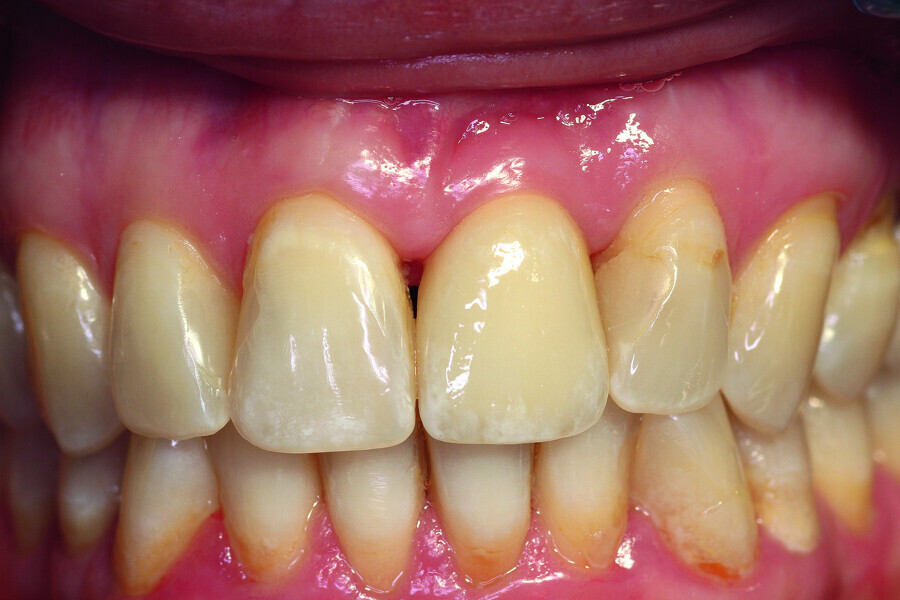

Fig. 11: The final result.